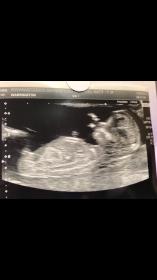

Baby boy or girl ?

Attachment 37717

Looks boyish